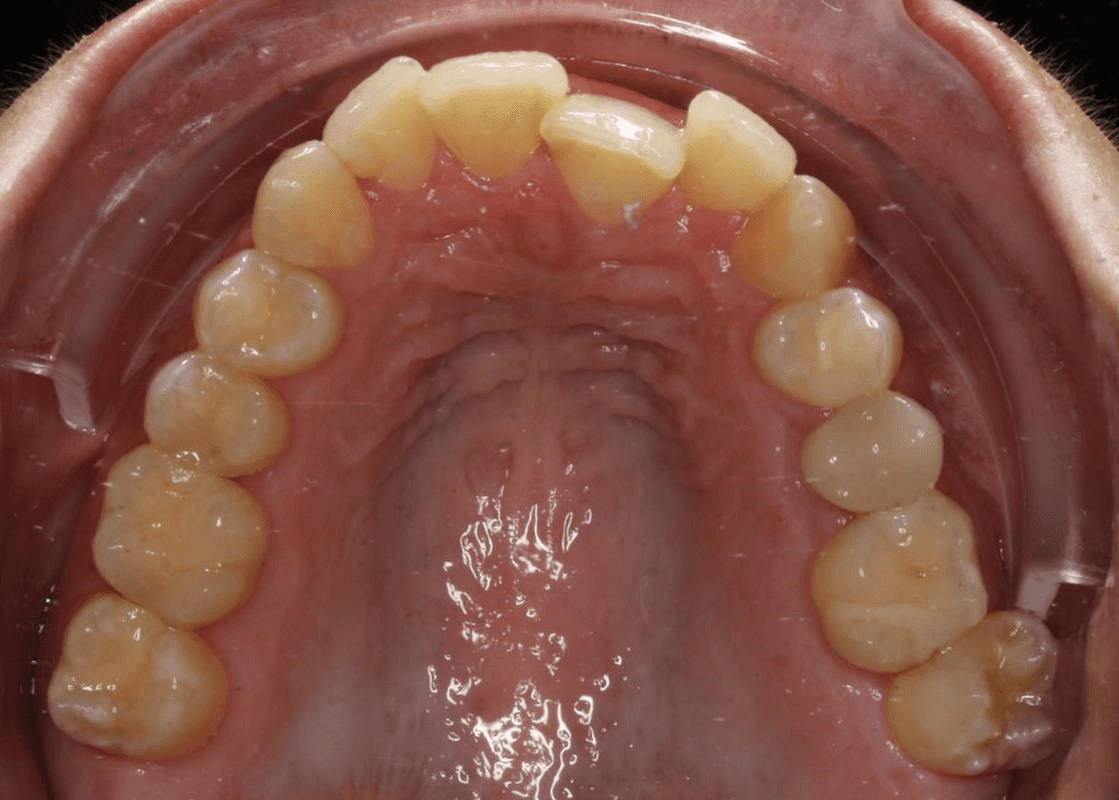

Initial treatment

INTRAORAL

Diganosis: Moderate crowding in both arches, constricted arch forms with anterior and posterior single tooth crossbites, poor smile display